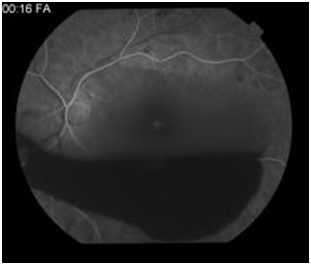

Figure 4: Early arteriovenous phase angiogram demonstrating hypofluorescence from a large blocking affect from preretinal hemorrhage.